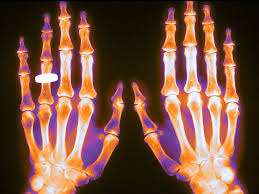

Eficacia de un programa poblacional de rastreo de osteoporosis en mujeres de 70 a 85 años

Se calculó el puntaje FRAX y se realizó densitometría a aquellas con riesgo de fractura elevado, dejando el tratamiento a criterio del médico de cabecera. Se logró una reducción del 28% (IC 11-41%) de las fracturas de cadera. The Lancet, 15 de diciembre de 2017

Densitometría ósea: poco cumplimiento de las recomendaciones

En este estudio argentino, la mitad de las densitometrías se pidieron en mujeres que no cumplían los criterios recomendados de edad o de riesgo aumentado para justificar el rastreo de osteoporosis. Salud Colectiva, octubre de 2016